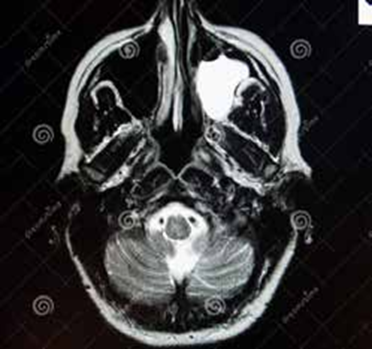

L’échographie abdominale réalisée objectivait une vésicule à paroi fine siège de plusieurs mini-calculs (Figures 1, 2).

La tomodensitométrie abdominale avec opacification confirmait cette cholécystite avec un foie hétérogène, siège de multiples microlésions arrondies hypodenses, rehaussées légèrement après injection de produit de contraste (Figures 3, 4).